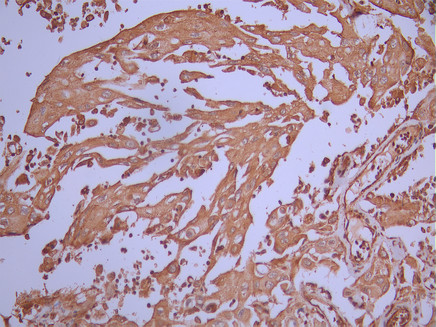

• IHC image of CSB-RA699080A0HU diluted at 1:100 and staining in paraffin-embedded human cervical cancer performed on a Leica BondTM system. After dewaxing and hydration, antigen retrieval was mediated by high pressure in a citrate buffer (pH 6.0). Section was blocked with 10% normal goat serum 30min at RT. Then primary antibody (1% BSA) was incubated at 4°C overnight. The primary is detected by a Goat anti-rabbit polymer IgG labeled by HRP and visualized using 0.05% DAB.